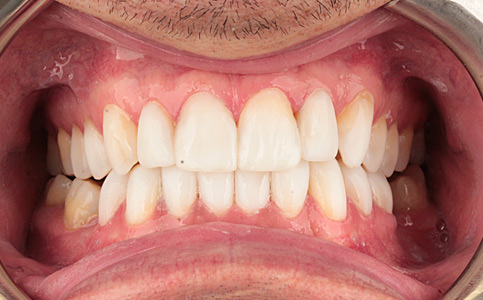

Pacjent zgłosił się do naszego Centrum stomatologii i Ortodoncji FRESHmed w Katowicach w celu poprawnia estetyki swojego uśmiechu. Po konsultacji i dokładnej diagnostyce, usunięto zęby dolne z powodu duzej ruchomości. Zęby zostały zastąpione 6 implantami zębowymi, na których odbudowano cały łuk zębowy dolny metodą All-on-6. Poprawę kształtu i koloru zębów górnych uzyskano poprzez zacementowanie koron pełnoceramicznych.

Zobacz efekty przeciągając suwak w prawo lub w lewo.